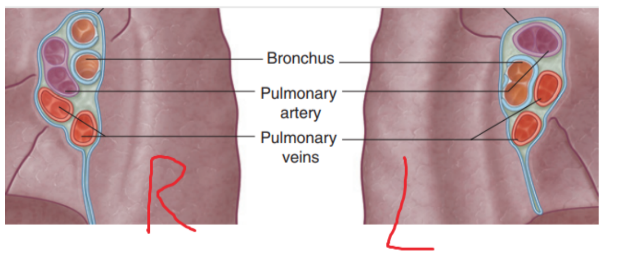

Lungs — general

Lie on either side of the mediastinum and surrounded by the pleural cavities

Air enters them via the main bronchi

Pulmonary arteries deliver deoxygenated blood to the lungs from the right ventricle, while oxygenated blood returns to the left atrium via the pulmonary veins

Root + hilum

The root —

A short tubular collection of structures attaching each lung to structures in the mediastinum

Covered in a sleeve of mediastinal pleura reflecting onto the lung surface as visceral pleura

Originates the pulmonary ligament — thin blade-like pleural fold projecting from the root towards the mediastinum, functioning to stabilize the position of the inferior lobe

The hilum —

The region outlined by this pleural reflection on the medial lung surface — where structures enter & leave

Structures we can find in each root & hilum —

Pulmonary artery

2 Pulmonary veins

Main bronchus

Bronchial vessels

Nerves

Lymphatics

The pulmonary artery is in most cases found at most superior portion of the hilum, while the pulmonary veins are inferior & the bronchi are posterior

On the side side however, the lobar bronchus to the superior lobe branches from the main bronchus in the root, unlike on the left where it branches in the lung itself superiorly to the pulmonary artery